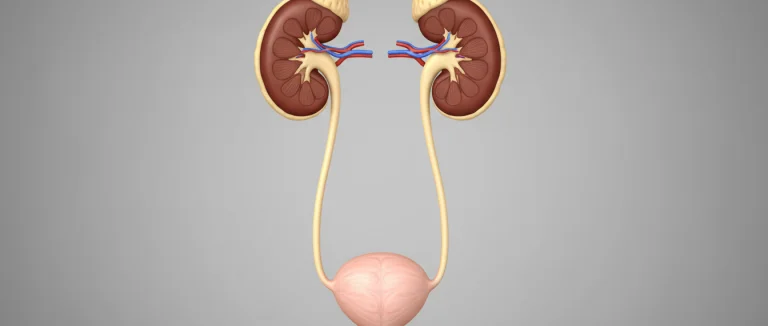

- УЗИ почек и мочевого пузыря – быстрый и безболезненный способ оценить структуру органов.